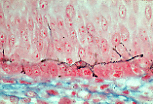

A型角化复层扁平上皮(掌部皮肤)的各层结构发育完善,易于识别。 | |

基底层 主要由柱状细胞构成,其基底面有微小的插入突起,有助于表皮与基膜的黏附。 | |

棘层 中的细胞呈多角形,嗜酸性,通过指状细胞突起相互嵌合。 |

薄切片(2微米厚)可清晰显示棘层的嵌合结构,其“齿状”部分由相邻角质形成细胞的突起构成。 这些突起处可见结节状增厚结构(比佐泽罗小体)。 | |

颗粒层 中的角质形成细胞核固缩,细胞质内充满透明角质颗粒(丝聚合蛋白原)。 | |

角质层 (A型角化上皮,掌跖区)由多层无核角质形成细胞堆叠而成, 细胞内充满角蛋白,构成防水的屏障结构。 | |